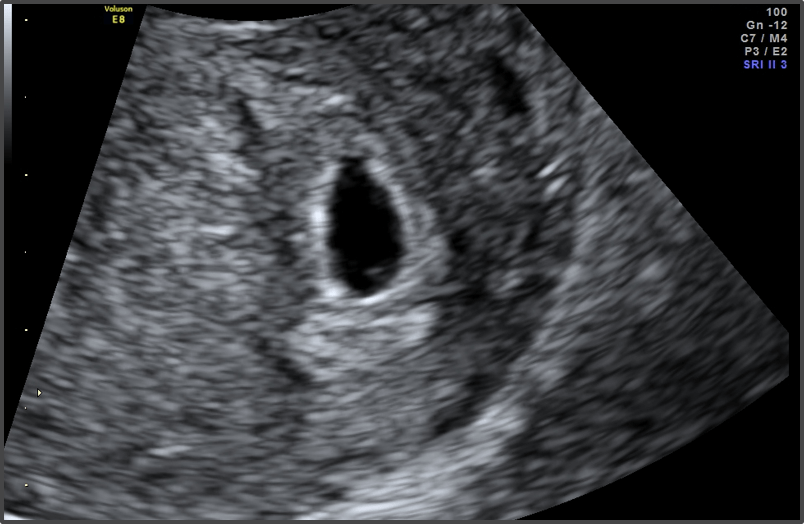

Pregnancy Calculator - Week 5

Baby is the size of Sesame seed

Approx Baby Size: 1.5 mm

Your baby is now the size of a sesame seed.